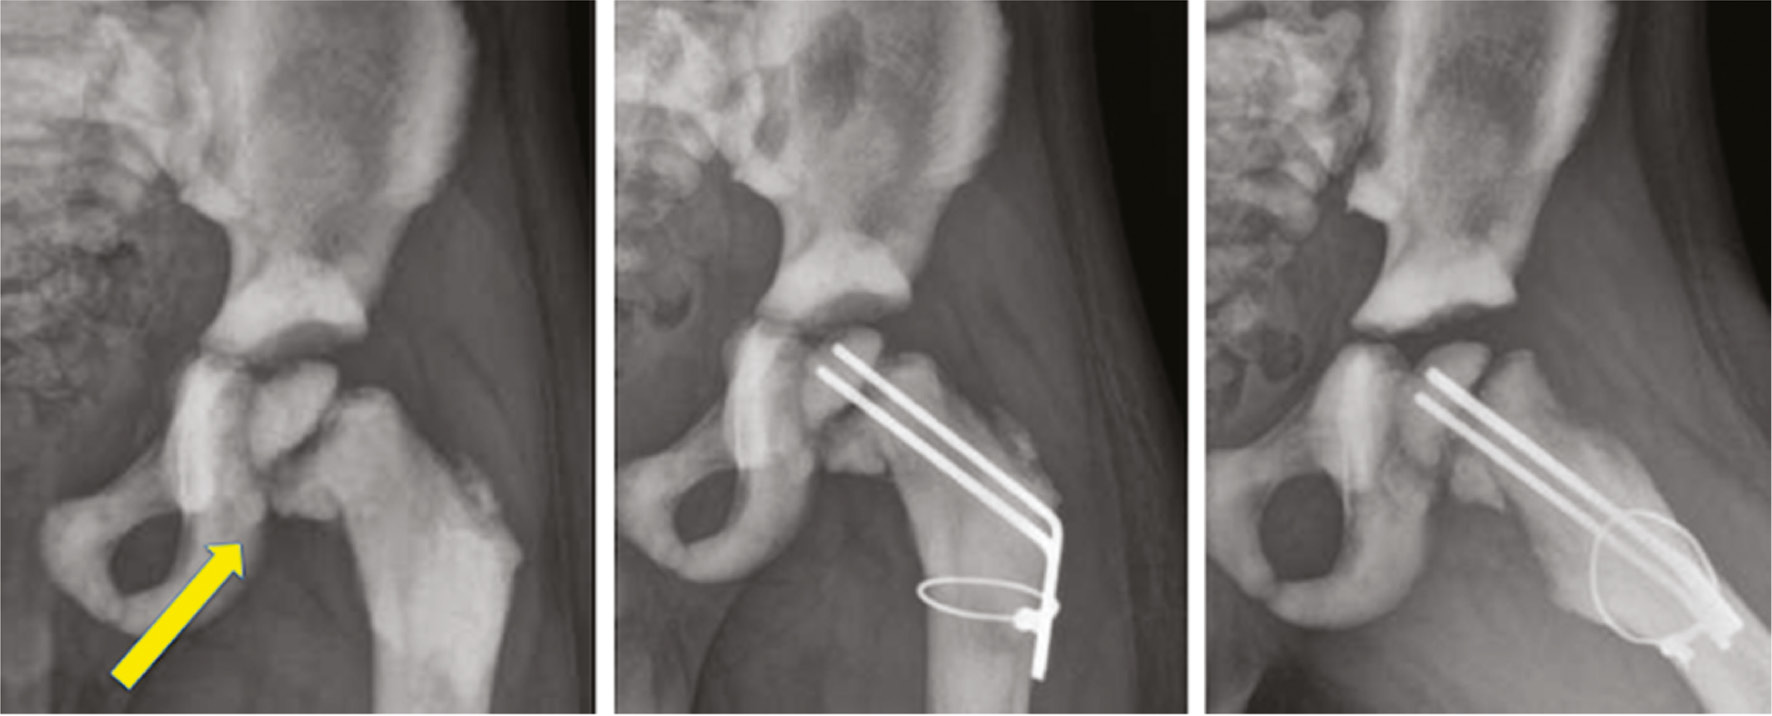

Figure 1. This 3-year-old with osteopetrosis and a femoral neck fracture was treated with K-wire fixation, bending the wires to the shaft and wiring.

Pins can also be used to effectuate a reduction via the Kapandji method or with temporary intraoperative olecranon pin traction (Figures 4 and 5).

Figure 4. This 9-year-old with a supracondylar humerus fracture was reduced with a posteriorly placed K-wire as a joy-stick. The medial pin was placed through a small incision to avoid ulnar nerve injury.

Figure 5. This 12-year-old with a supracondylar humerus fracture required a temporarily placed olecranon pin to gain traction while a Kapandji wire leveraged the fracture to a reduced position. Medial pins were placed through an incision and the pins were cut off below the skin. Adolescent fractures often require more than 3 weeks of pin fixation and are at increased risk of infection. These pins were buried to prevent pin tract infection and possible joint sepsis.